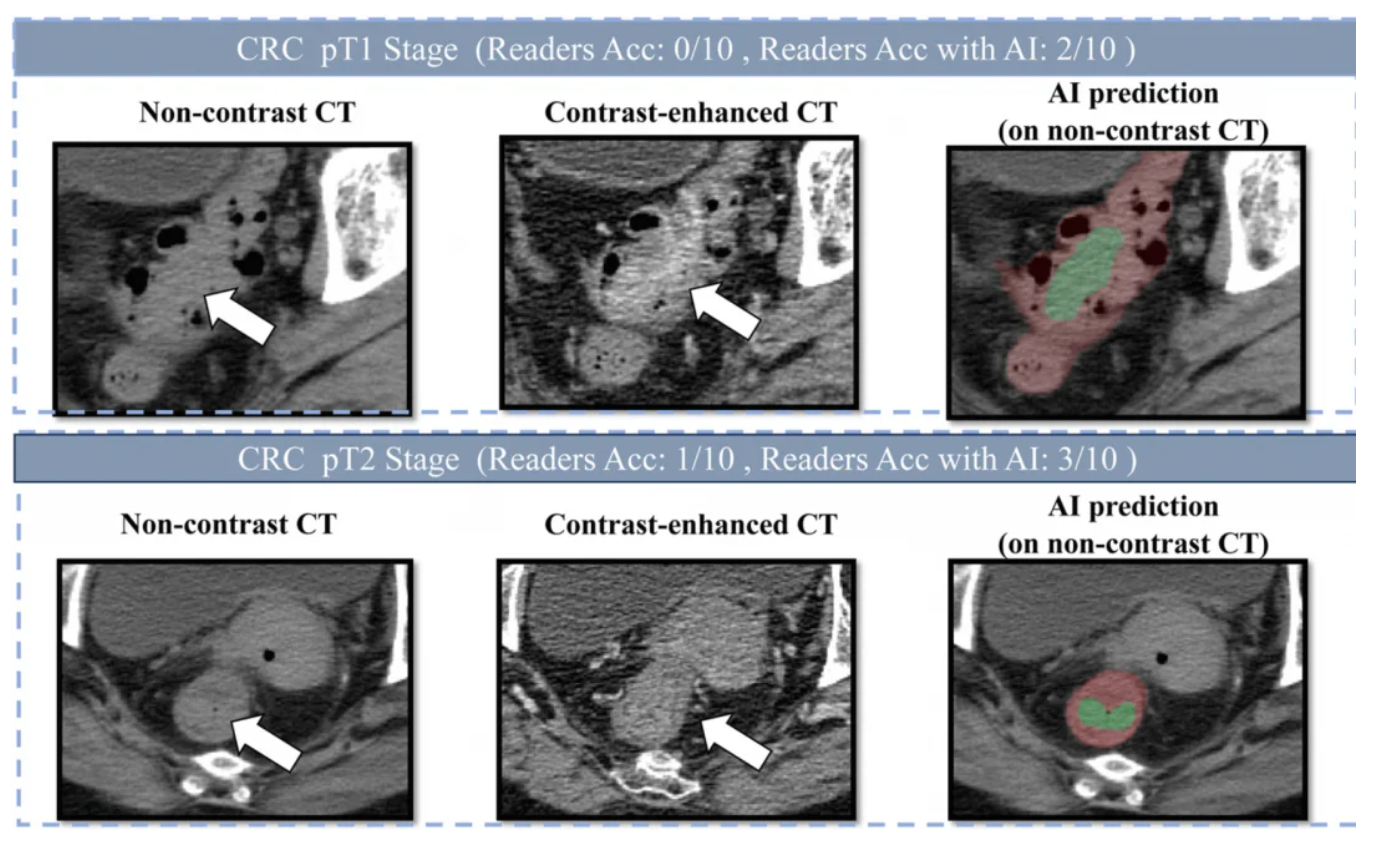

- 碾压人类医生: 在对比测试中,它的准确率比 10 位不同年资的放射科医生平均高出 20.4%。如果有 AI 辅助,医生的看病水平还能再飙升 14.5%。